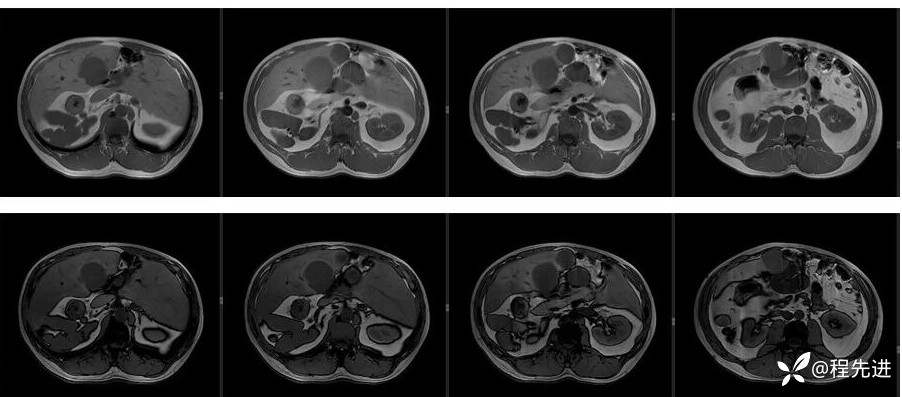

辅助检查:上腹部平扫+增强扫描提示:肝脏、脾脏、胰腺 、胃十二指肠左右倒置,脾脏形态失常,呈分叶团块状,考虑发育变异。肝左右交界区多发肿块,考虑:上皮样血管内皮瘤可能性大,或转移瘤?其它?请结合临床。脂肪肝。肝门胆管局限性扩张。胆囊折叠,壁稍增厚,慢性炎症?胰腺下方椭圆形结节,副脾?

影像检查